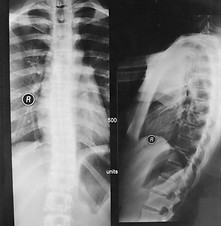

Below is an example of a patient who has undergone successful scoliosis treatment. The X-ray images show the before and after picture of a 13 year old scoliosis patient with cobb angle of 38 degree. She grew from 1.62m to 1.71m during 14 months of treatment and saw the curvature of her spine significantly reduced.

BEFORE TREATMENT

The spine is curved before treatment.

AFTER TREATMENT

Curvature of the spine is barely visible at the end of the treatment.